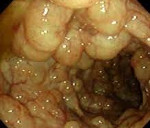

Пневматоз кишечника – редкое заболевание ЖКТ, при котором кишечные газы проникают в толщу стенки органа и образуют в ней воздушные полости. Чаще патологический процесс локализуется в подслизистом или субсерозном слое толстой или тощей кишки. Заболевание может поражать людей всех возрастов, но преимущественно встречается у младенцев и пожилых людей ввиду пониженной физической активности и частых нарушений в работе пищеварительной системы. Размеры воздушных кист могут варьировать от 0,5 до 5 см в диаметре. По распространенности процесса пневматоз разделяют на ограниченный, затрагивающий одну область кишечника, и диффузный. Последний характеризуется равномерным распространением патологических образований по всей площади кишечного тракта.

В гастроэнтерологии наибольшее признание получила механическая теория пневматоза. Согласно данной концепции, воздушные кисты кишечника возникают при первичной патологии ЖКТ (опухоль, энтероколит, стеноз) и врожденных дефектах кровеносных и лимфатических сосудов кишки. На фоне заболеваний ЖКТ происходит травматизация и истончение внутренней оболочки кишки. Газ под воздействием внутрикишечного давления проходит через микродефекты, попадает в подслизистые лимфатические сосуды и распространяется с помощью перистальтики в подслизистом слое кишечника. Кисты изнутри выстланы эпителием и могут содержать различные газы: азот, кислород, водород, аргон, двуокись углерода и др.

При ограниченном пневматозе кишечника ввиду отсутствия выраженной специфической симптоматики диагностика затруднительна. При возникновении болей, нарушении процесса пищеварения пациентам необходима консультация гастроэнтеролога. Специалист проводит комплексный осмотр, изучает анамнез заболевания и сопутствующую патологию, обращая особое внимание на болезни ЖКТ. В некоторых случаях при глубокой пальпации живота удается прощупать небольшие округлые образования, идущие вереницей вдоль кишечного тракта, напоминая гроздь винограда. Для установления диагноза проводятся следующие исследования:

- Колоноскопия. Эндоскопическое исследование позволяет визуализировать газовые пузырьки, оценить масштабы поражения и состояние слизистой оболочки ЖКТ. При необходимости эндоскопист проводит биопсию участка кишки для гистологического анализа.